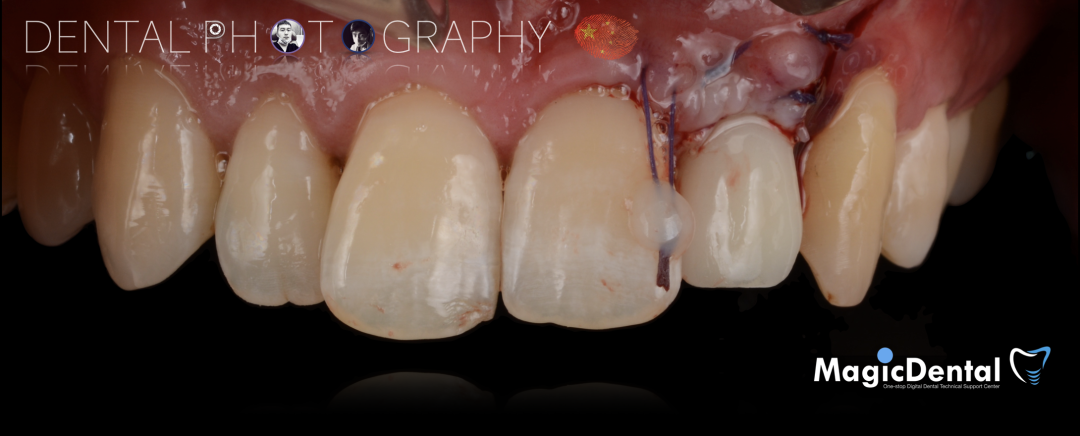

导板就位,种植窝洞预备,植入Nobel Active 3.5*15mm种植体一枚,植入扭矩35N,安装临时基台。

口外制作树脂临时冠,抛光。安放树脂修复的临时冠,调整正中、前伸、侧方均无咬合干扰。

术后3个月CBCT及X线片。

术后三个月口内正面像